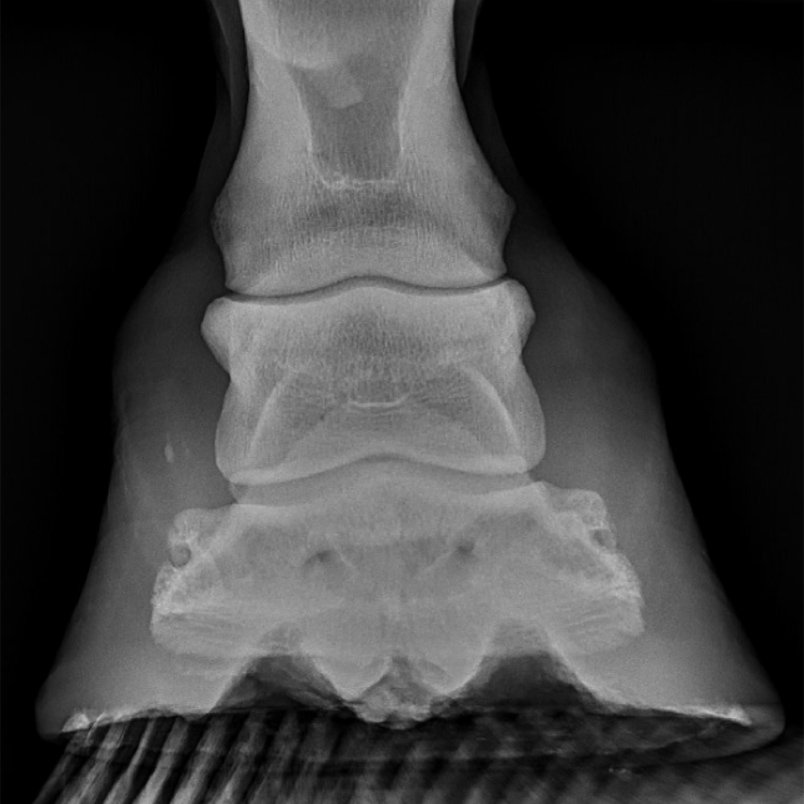

PPT Equine Imaging PowerPoint Presentation, free download ID330603 Horse Hoof Keratoma They should be suspected whenever a horse is suffering from a. In horses, a keratoma is a benign epithelial tumor of the hoof capsule. Cylindrical keratomas look like columns. A keratoma is a benign tumor of the hoof that grows inside the horse's foot. A keratoma is a rare, benign tumour that is found within the foot. It consists of. Horse Hoof Keratoma.

Understanding keratoma in a horse's hoof Horse & Hound Horse Hoof Keratoma They should be suspected whenever a horse is suffering from a. A keratoma is a rare, benign tumour that is found within the foot. It consists of abnormal masses of keratin (the main. Keratoma of the hoof is a uncommon cause of persistent lameness in the horse. Keratomas in horses are abnormal growths or benign tumors that develop within the. Horse Hoof Keratoma.